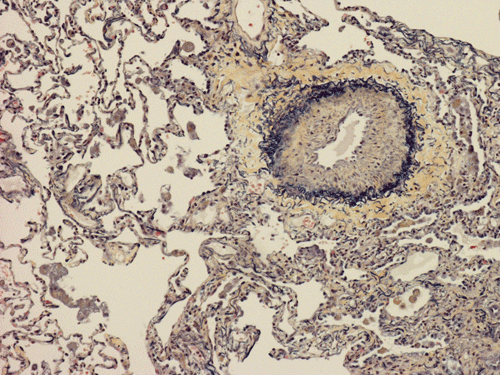

At scanning magnification (Panel A), the lung parenchyma is replaced by some coalescing fibrous nodules. The degree of involvement is variable at different fragments (Panel B and C). In the less affected areas, there are some fibrotic thickening of the septa (Panel C). In some areas, the changes are minimal and the pleural appear to be uninvolved (Panel D and E). In low to medium magnifications, these nodules of fibrosis contains a large number of hemosiderin laden macrophages (Panel F and G) admixed with fibrous tissue. The diagnostic tissue, however, is present in areas with increased cellularity. In these areas, there is a background of cells with a moderate amount of cytoplasm and bland nuclei. Some of these nuclei have kidney shape (arrow in Panel H). In some areas, many of the nuclei have a deep nuclear groove that resemble a coffee bean (arrow in Panel I). In the third type of areas, the nuclear grooving is not distinct (Panel J). Prominent eosinophilic infiltrations are almost always present. Immunohistochemistry on CD1a revealed many positive cells (Panel L). Also present in the specimen are multiple small blood vessels with thickened intima (Panel K). A Movat pentachrome stain demonstrates an internal elastic layer in these vessels and confirms that these are arteries (Panel M and N).

In the end stage, the exhausted lesions are predominantly fibrotic and largely depleted of LCs. In some regions, the fibrosis may surround cystic spaces of variable diameter to form large areas of honeycombing. This is especially predominant in the upper lobes. In cases where parenchymal scaring is present, the pulmonary function will be largely compromised. At this stage, both pulmonary function tests and radiologic findings may suggest diffuse lung disease, but biopsy will show stellate fibrotic lesions centered on the terminal airways with no identifiable interstitial inflammation. Pulmonary vasculopathy (in areas of lung remote from parenchymal nodules) is also seen in late stage PLCH. Vasculopathy manifests as intimal fibrosis, medial hypertrophy or luminal obliteration involving both venules and arteries. This may account for pulmonary hypertension seen late in PLCH.